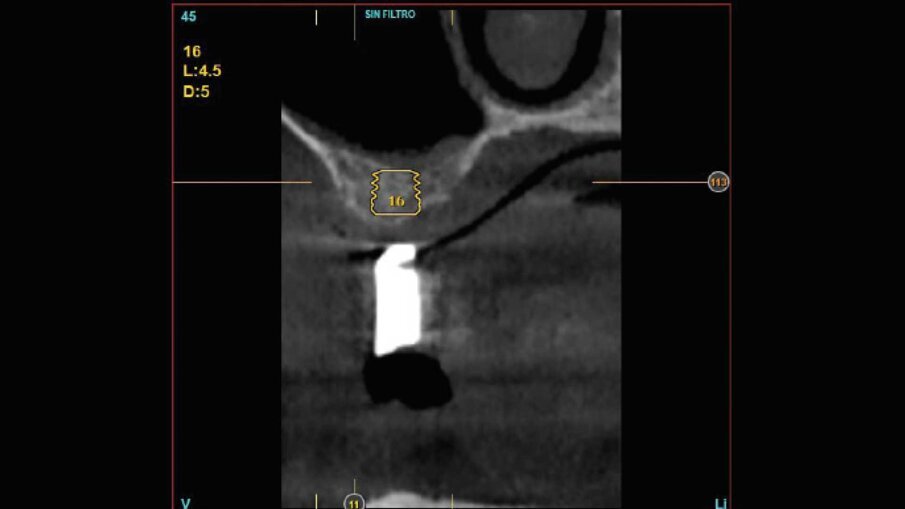

Al paziente fu spiegato che la strategia migliore consisteva nell’estrazione di tutti gli elementi dentari e l’inserimento di sei impianti in ogni arcata dentaria e successivamente il ripristino delle arcate con due protesi tipo Toronto. Si decise di non estrarre subito i quattro canini perché sarebbero serviti per stabilizzare le mascherine chirurgiche durante la chirurgia. Lo studio del caso e la sua realizzazione fu fatta con metodo analogico. Due modelli in gesso furono montati alla giusta dimensione verticale e fu realizzato il montaggio dei denti per visualizzare il risultato finale (Fig. 3). Dal montaggio dei denti furono realizzate le mascherine chirurgiche che sarebbero state utilizzate per gli esami radiografici tridimensionali e avrebbero guidato il posizionamento degli impianti durante la chirurgia. All’esame radiografico tridimensionale (Figg. 4-7) si notava la presenza di una quantità esigua di osso coronalmente ai seni mascellari e al nervo alveolare inferiore. Si decise di inserire impianti extracorti 4,5 mm di lunghezza in queste zone, per evitare sia impianti inclinati sia cantilever molto estesi. Lo studio della scala dei grigi, o scala Hounsfield, mostrava una densità ossea tale da consentire il carico immediato anche in queste zone. Ovviamente sarebbe stata necessaria la conferma intra-operatoria valutando clinicamente la compattezza dell’osso tramite la fresatura.

La fase chirurgica fu eseguita circa due mesi dopo le estrazioni. Al paziente fu somministrata terapia antibiotica preventiva dalla mattina dell’intervento chirurgico e protratta per sei giorni. Fu somministrata anestesia locale con Articaina 1:100000 e adrenalina al 2%. Furono scollati lembi a tutto spessore e furono inseriti sei impianti BTI Core in ogni mascellare. Fu eseguito prima l’intervento sul superiore e dopo un mese sull’inferiore su richiesta del paziente che aveva paura di postumi eccessivi. Gli impianti furono posizionati con l’ausilio delle mascherine chirurgiche (Figg. 8, 9) che furono usate per la registrazione della posizione degli impianti secondo la metodica del modello modificato descritta dal dott. Lionello Biscaro. La posizione risultava molto accurata grazie alla stabilizzazione offerta dai canini residui che furono estratti subito dopo l’inserzione degli impianti per consentire la registrazione della posizione relativa degli impianti (Figg. 10, 11). In particolare nella posizione del dente 16 fu inserito un impianto BTI Universal-Plus 5 mm di diametro

x 4,5 di lunghezza, in posizione 26 un impianto BTI Core 3,75 x 6,5 mentre in posizione 36 e 46 furono inseriti due impianti BTI Core 4,75 x 4,5. La superficie UnicCa degli impianti fu bagnata con frazione F2 ottenuta dal plasma per centrifugazione del sangue del paziente. Furono avvitati i pilastri Multi-Im e furono fatte le registrazioni necessarie a comunicare al tecnico la posizione degli impianti rispetto ai modelli già montati e la posizione reciproca degli impianti, secondo la tecnica del modello modificato citata precedentemente. I pilastri di guarigione furono avvitati, le suture applicate e il paziente fu dismesso.